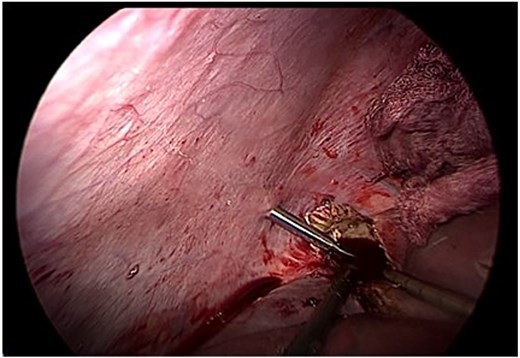

Given the size and location of the cyst, complete pericystectomy was not indicated due to proximity to major vascular structures and the absence of complications. Instead, careful evacuation of the membrane and limited resection of prominent pericystic tissue was performed, preserving liver integrity (Fig. 4). A drain was left in place due to the potential for undetected biliary communication.

Careful evacuation of cystic material and limited resection of prominent pericystic tissue. Complete pericystectomy was not indicated due to cyst size and location.